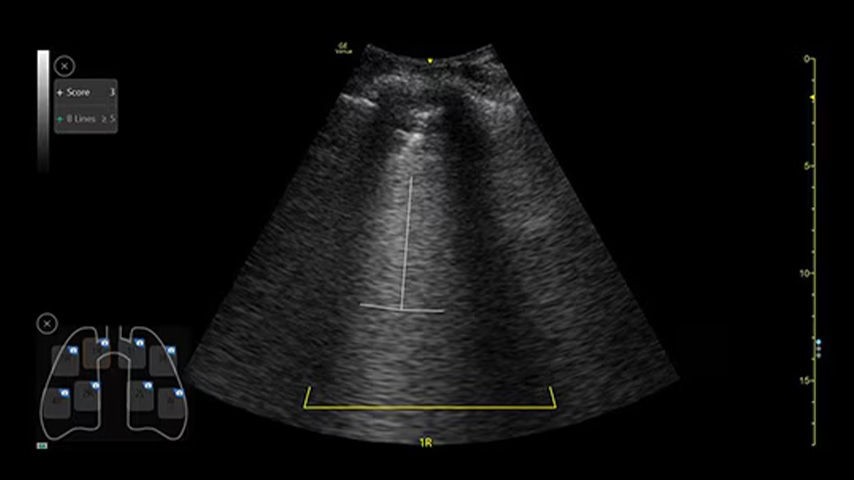

Highlight and count B-lines, in real time

With the Auto B-Lines tool, you can calculate overall lung score in one step. Use it in conjunction with Lung Sweep to highlight B-lines and display the frame with the most B-lines per rib space.